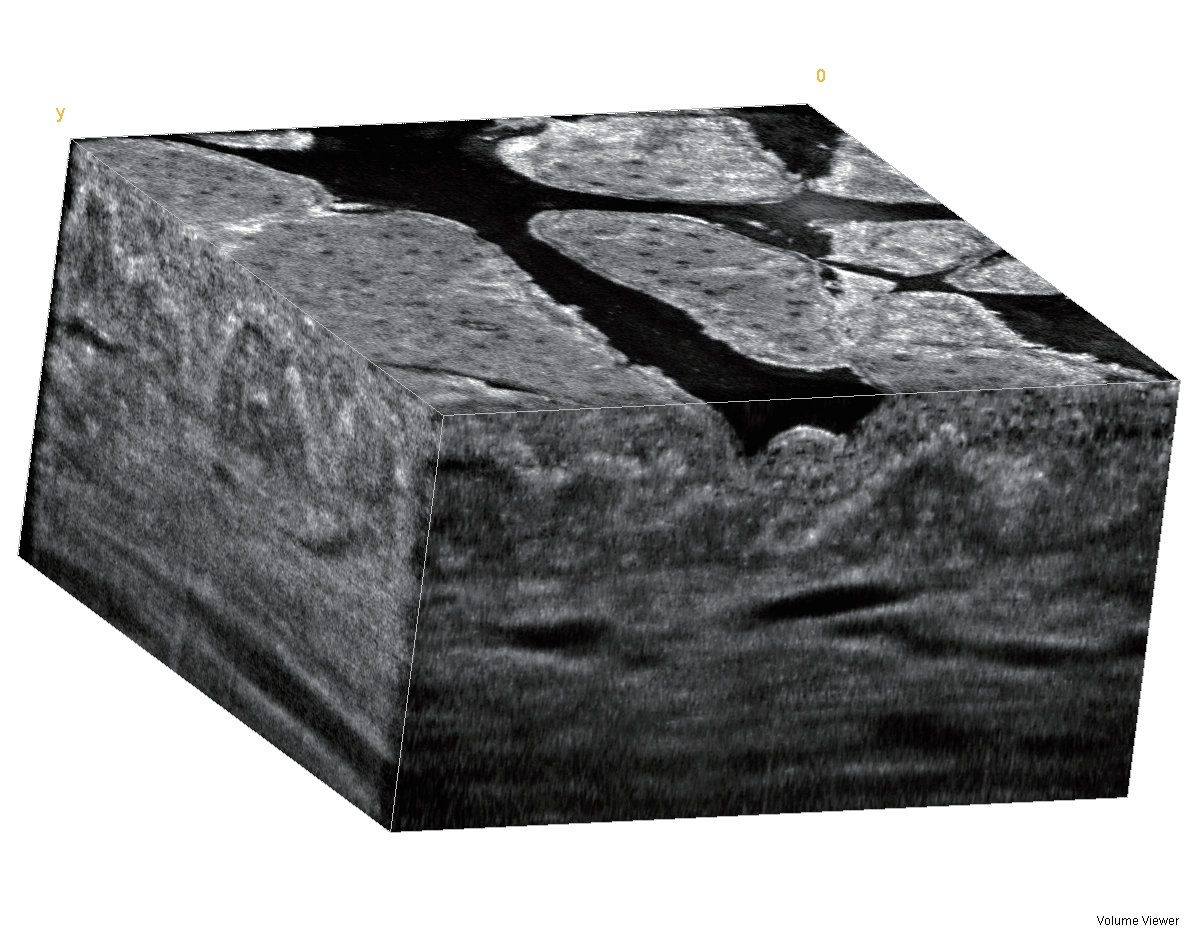

? ? TPM DUB系統15-18 MHz掃描的皮膚圖像,清晰地顯示和測量皮膚全層的影像。Gel-耦合劑,EP-表皮,DER-真皮,HYP-脂肪,FAS-淺筋膜,MSC-肌肉

?TPM 22兆赫茲超聲,掃描深度達40毫米,分辨率72微米以下,覆蓋HFUGUS或稱為合二為一,同時具有彩色多普勒功能,必將成為皮膚科和醫學美容醫生迫切需要的超聲影像可視化、量化手段。